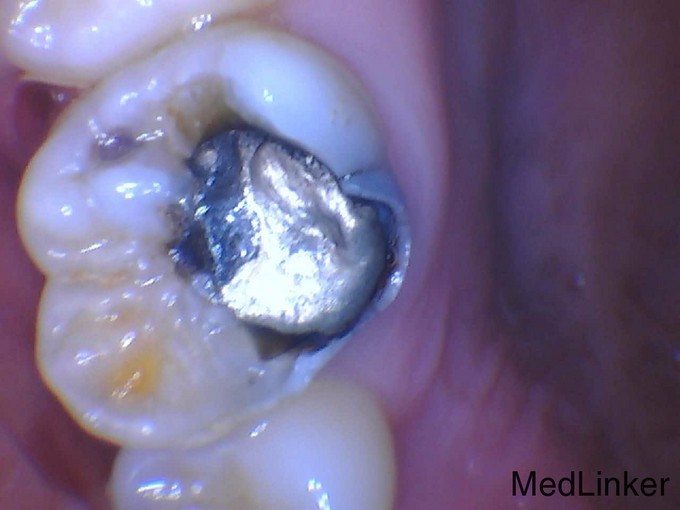

继发龋图片

继发龋图片,

远中牙合面充填物,远中牙体缺损,边缘继发龋坏,冷热测敏感,叩)

1113大面积充填后继发龋的嵌体修复光36

第一前磨牙第二前磨牙继发龋树脂再充填1例